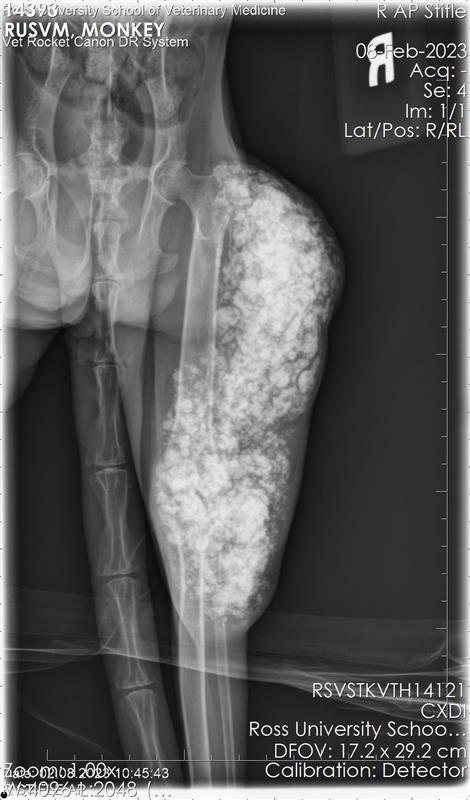

On postmortem examination, the carcass weighed 3.83 kg and had a body condition of 2 out of 5. The swollen area on the right pelvic limb exhibited mild alopecia and crusting. Postmortem radiographs showed an extensive, multilocular radiopaque mass within soft tissues surrounding the latero-caudal

aspect of the right hip and stifle, extending from the level of the greater trochanter to approximately 10 cm distal to the tibiofemoral joint. The mass did not invade long bones.

Dissection revealed a multilobulated, non-encapsulated, crepitant, yellow to red mass measuring 11 x 5 x 4 cm, infiltrating and replacing the subcutaneous tissue and skeletal muscles of the right thigh.

The mass contained numerous hard, white spicules, suggesting mineralization. The periosteum of the right femur was focally and extensively irregular. No gross pathological alterations were observed in the internal organs.